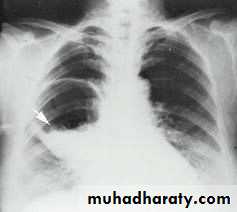

Hydated cyst (simple)

Hydatid cyst (water lily sign)